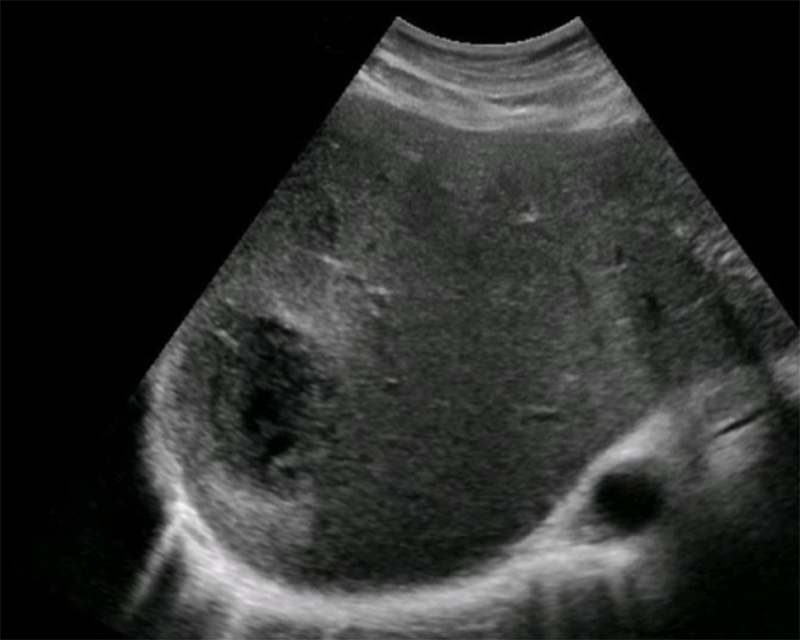

- Mechanical Risk Factors for Delivery

Figure 29. Transverse suprapubic view revealing the fetal cranium in the pelvis, consistent with a vertex presentation. Note the calipers measuring a bi-parietal diameter at 30 weeks and 6 days.

- Non-vertex (breech, transverse, or oblique) increases risk of difficult delivery and complication25

Figures 30A & B. Suprapubic views revealing no fetal cranium in the pelvis. While in some cases like this transverse view of a breech presentation (A) and this sagittal view of a transverse presentation (B), it may be difficult to exactly determine the fetal anatomy, the lack of the fetal cranium is adequate to rule out a vertex presentation and should increase the clinician’s suspicion for a more difficult delivery.